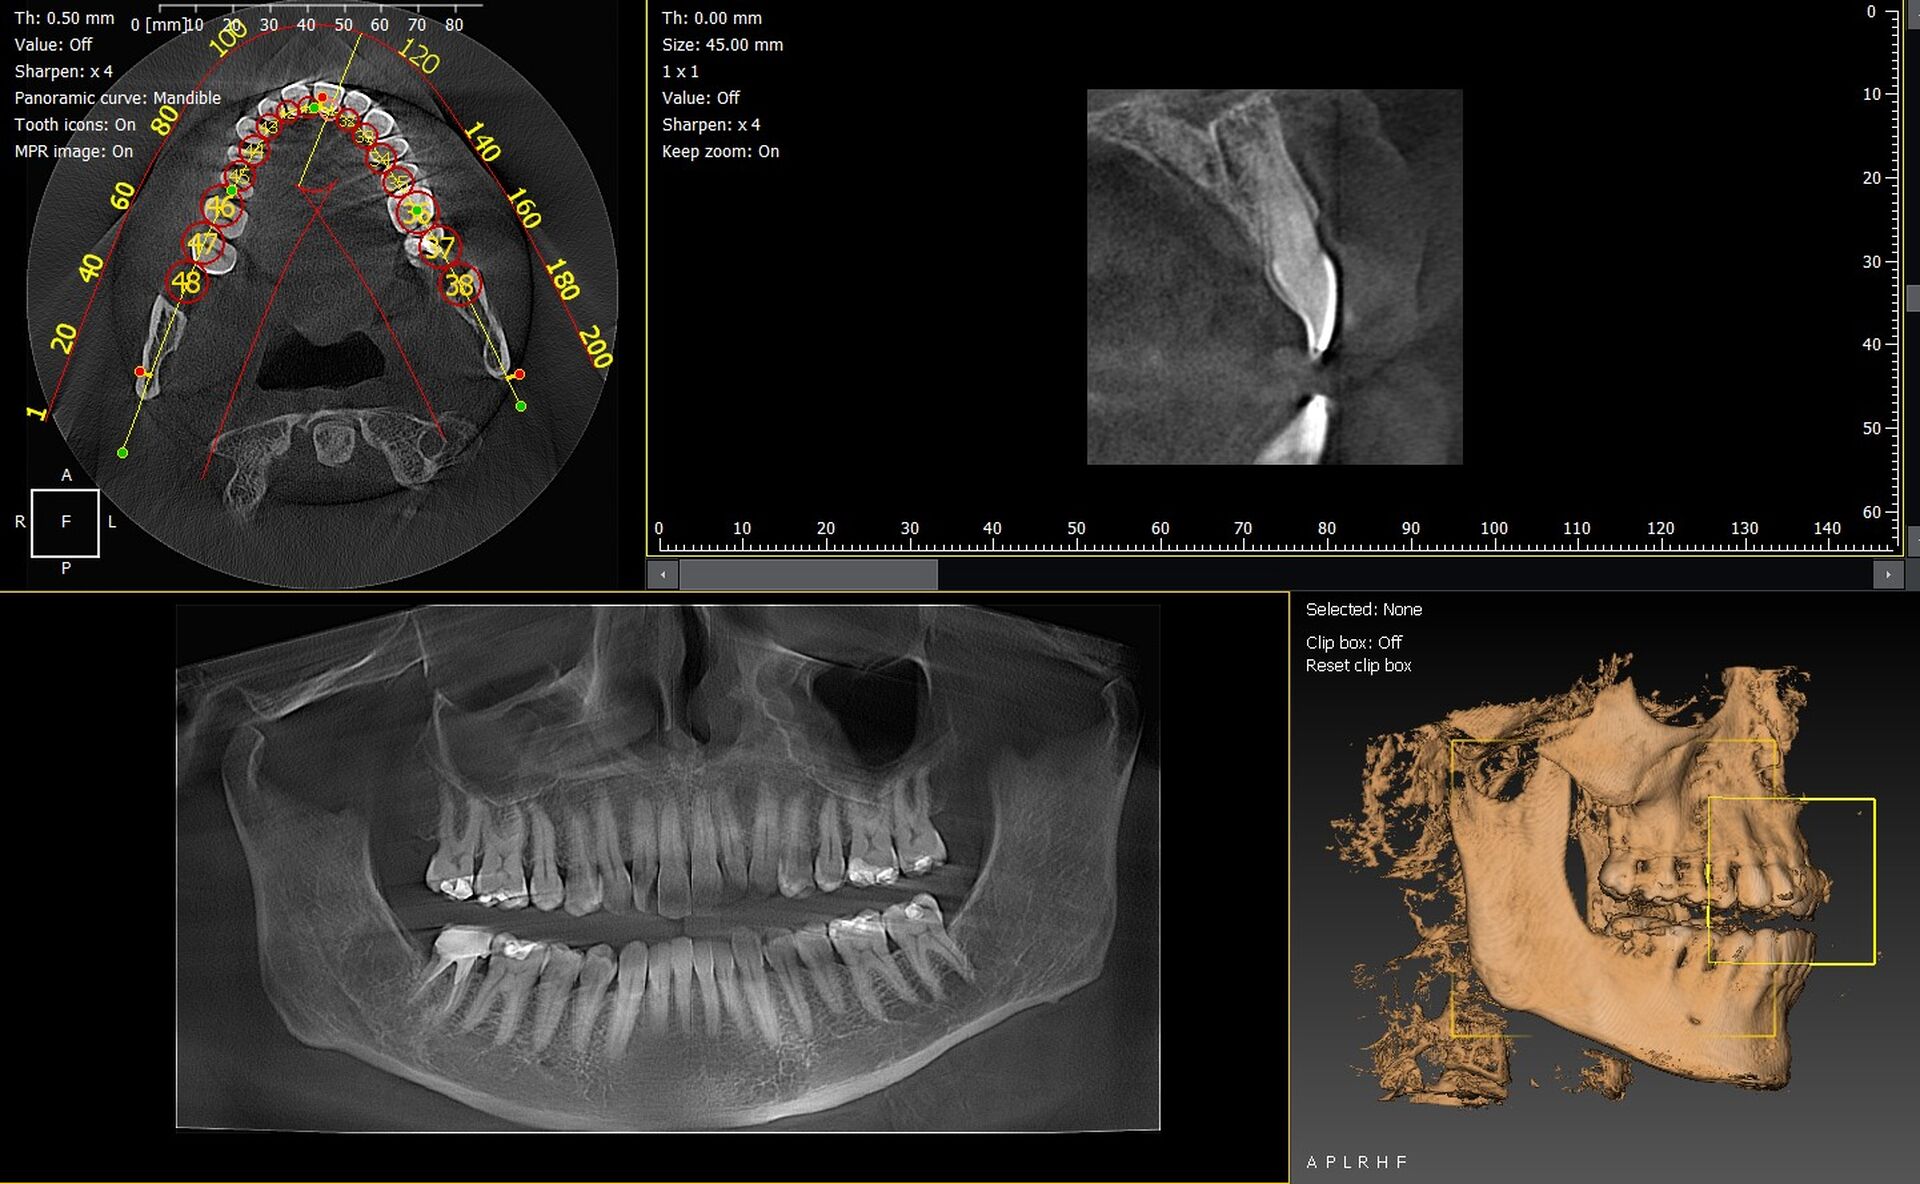

Les cabinets dentaires de Sisteron et du département des Alpes de Haute Provence 04 cherchent à renforcer la précision de leurs diagnostics grâce à l’imagerie 3D. Les systèmes CBCT permettent une analyse volumétrique détaillée, essentielle pour l’implantologie, l’endodontie, la chirurgie orale ou encore l’orthodontie. Parmi les solutions les plus performantes, les modèles Dürr Dental VistaVox et Owandy I-Max 3D se distinguent par leur fiabilité, leur ergonomie et la qualité de leurs images.

Dürr Dental VistaVox : une imagerie 3D complète pour diagnostics avancés

Le VistaVox assure une précision remarquable grâce à son volume d’acquisition optimisé pour couvrir l’arcade complète. Il offre une visualisation idéale du canal mandibulaire, des sinus et des zones anatomiques complexes.